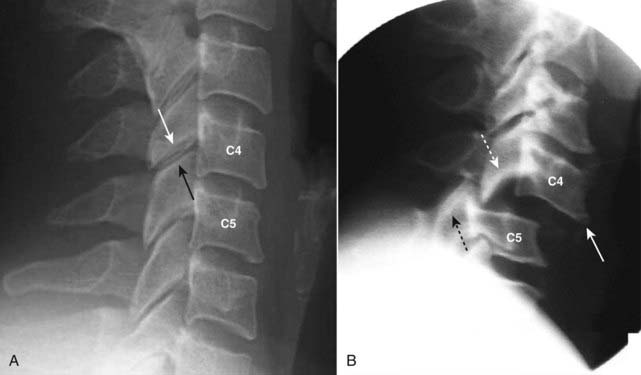

image Bilateral locking of the facets in the cervical spine can occur as a result of a hyperflexion injury in which the inferior facets of one vertebral body slide over and in front of the superior facets of the body below. In this position, the slipped facets cannot return to their normal position without medical intervention; thus, the term “locked.”

image Locked facets occur with forward slippage of the affected vertebral body on the body below it by at least 50% of its AP diameter.

imageOn lateral (sagittal) imaging of the cervical spine, the inferior articular facets will lie in front of the superior facets of the body below. This is the reverse of the normal anatomic relationship between adjacent facets (Fig. 24-21).

image Since the superior articular facets are no longer “covered” by the inferior facets above them, this appearance was described on CT as the naked facet sign.

image This injury virtually always results in neurologic impairment.

image

Figure 24-21 Normal and bilateral locked facets.

A, Normally, the inferior articular facet of the body above (in this case C4, solid white arrow) lies posterior to the superior articular facet of the body below (in this case C5, solid black arrow). B, The inferior articular facet of C4 (dotted white arrow) lies anterior to the superior articular facet of C5 (dotted black arrow), the reverse of normal. Locking of the facets in the cervical spine can occur as a result of a hyperflexion injury that results in forward slippage of the affected vertebral body on the body below it by at least 50% of its AP diameter (solid white arrow).